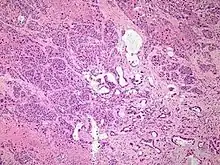

Micrograph of an adenosquamous carcinoma of the lung. The adeno- or glandular component is on the left of the image and the squamous component on the right of the image. H&E stain.

Light microscopy shows a combination of gland-like cells and squamous epithelial cells.[4] On immunohistochemistry, it is typically positive for CK5/6, CK7 and p63, and negative for CK20, p16 and p53. On genetic testing, KRAS and p53 are typically altered.[4]